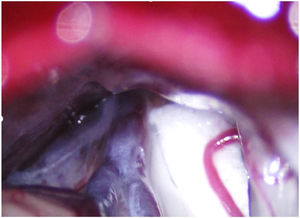

Leal et al.73 proposed a classification of neurovascular compression in classical TN (Fig. 5): grade I, simple contact; grade II, nerve distortion or displacement; grade III, vessel causing a large groove on the nerve. Only grades II and III are considered to constitute true compression (Fig. 6). The MVD procedure, which was proposed by Gardner and developed by Jannetta, begins with the performance of a craniotomy of 2−3 cm in the posterior fossa, accessing the cerebellopontine angle cistern via a retromastoid approach. Cranial nerves are identified with an operating microscope, and neurophysiological stimulation can be used to identify the facial nerve. Once the neurovascular conflict is located, microdissectors are used to separate the vascular structure from the nerve. To avoid further contact and ensure continued prevention or damping of the arterial pulsation, microsurgical Teflon pieces are placed (Fig. 7) and fixed with fibrin. The global rate of complications in MVD procedures ranges from 10% to 23%, although some studies report that complications are extremely rare in centres with experience performing surgery for TN.74,75Table 14 summarises safety and effectiveness data for some of the most frequently used surgical techniques for TN.7,41,74–76

Intraoperative microscopy image of a grade III neurovascular conflict (groove on nerve) between the superior cerebellar artery and the root entry zone; image taken during a microvascular decompression procedure in a patient with refractory trigeminal neuralgia affecting the V2 branch (Hospital de la Santa Creu i Sant Pau).